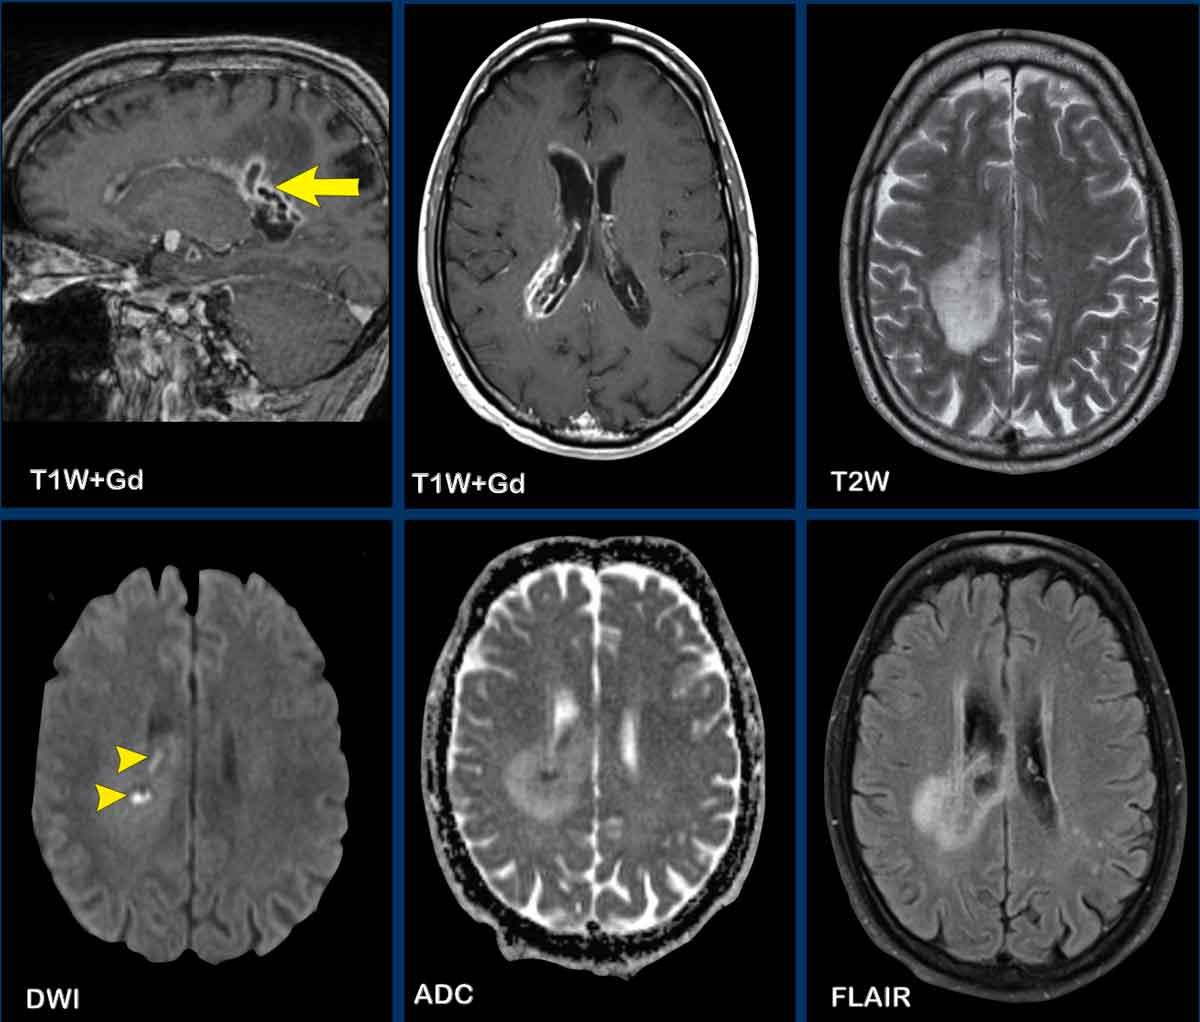

Các hình ảnh này của bệnh nhân có áp xe vùng đỉnh.

Hình ảnh

Áp xe biểu hiện hạn chế khuếch tán trung tâm với thành ngấm thuốc tương đối dày.

Đầu mũi tên màu vàng chỉ vào lớp ngấm thuốc mỏng của thành não thất.

Kết luận

Áp xe lan vào trong não thất, dẫn đến viêm não thất.

Các hình ảnh này của bệnh nhân nam 63 tuổi, có áp xe não nhỏ (mũi tên vàng) tại trung tâm bán bầu dục bên phải.

Lưu ý có sự xâm lấn não thất đáng kể.

Bên cạnh ngấm thuốc thành não thất, còn ghi nhận hạn chế khuếch tán trong áp xe và trong lòng não thất (đầu mũi tên).